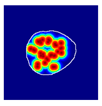

| True label: Crescentic |  |  |  |  |  |

| single-multiclass: Crescentic p = 0.999, IoU = 0.154 | |||||

| multiple-binary: Crescentic p = 1.000, IoU = 0.128 | |||||

| Spatially guided: Crescentic p = 0.979, IoU = 0.740 | |||||